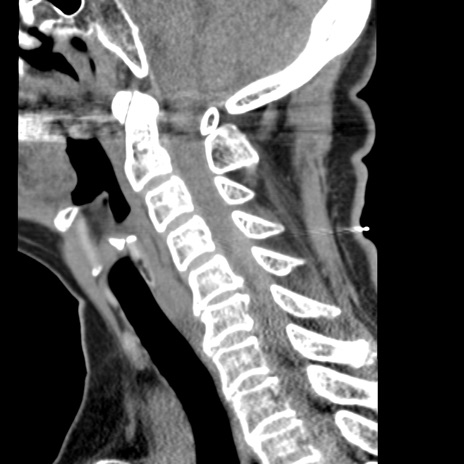

症例50 頚椎CT(矢状断像)

【症例】60歳代女性

【主訴】後頭部〜右後頸部にかけての痛み

【現病歴】本日飲食店でコーヒーを飲んでいたところ、突然後頭部〜右後頸部にかけて痛みが出現し、右上肢の感覚障害を伴ったため救急要請。

【身体所見】脳神経学的に明らかな異常所見を認めず。右上肢に軽度の感覚障害あり。

異常所見と診断は?

頚椎CT